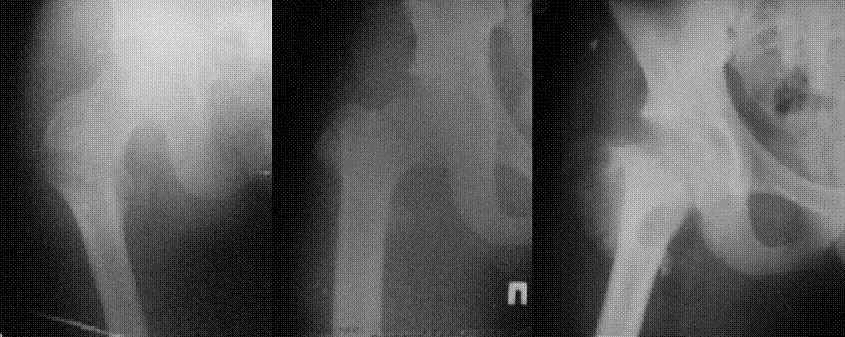

Уважаемые коллеги! Нужен совет.Больной Х., 21 год, ДЗ: ложный сустав вертельной области правого бедра.

Травма 8 мес. назад, ДТП, получил закрытый межвертельный перелом правого бедра. Лечился в городской больнице одного из городов-спутников г. Караганды скелетным вытяжением в течение 3 недель, затем кокситной гипсовой повязкой 2 мес. В настоящее время имеется укорочение конечности на 7 см, умеренная боль в вертельной области; ходит без костылей, полностью нагружая больную конечность, при нагрузке отмечается смещение дистального отломка проксимально примерно на 1,0 см.; объем движений в коленном суставе сохранен; при пальпации отломков боли нет, умеренная патологическая подвижность. Планируем внеочаговый остеосинтез спице-стержневым аппаратом, дистракция до восстановления длины бедра, вторым этапом остеосинтез стержнем Гамма. Есть надежда, что на дистракции пойдет сращение и у больного хватит терпения завершить лечение в аппарате.

В приложении пример пациента, близкого по картине к тому, что представил Виктор (варус и смещение периферического отломка на поперечник кзади). Сделали как раз то, что Виктор исходно намеревался - аппаратная коррекция и затем гамма.

Виктор! Судя по снимкам,укорочение не более 2-3 см (даже линия Шентона сохранена). При таком укорочении дистракционный остеосинтез аппаратом внешней фиксации на конкретном сегменте,действительно представляется агрессивным.Может быть,как предлагает D.Kuldjanov,ограничиться предоперационным скелетным вытяжением и после рентгенконтроля использовать Blade Plate или Гамму с губчатой аутопластикой.Возможна миотомия приводящих мышц.Смещение не столь велико,чтобы его форсированное устранение грозило неврологическими осложнениями.Даже остаточное укорочение в пределах 1см вряд-ли усложнит операцию и существенно повлияет на исход.Учитывая статус клиники,для пациента не менее важны комфортность в послеоперационном периоде,возможность полноценно жить и работать в период реабилитации, максимальное снижение вероятности послеоперационных осложнений.А этим условиям аппарат Илизарова не отвечает.

Если судить по снимкам, то укорочение кажеться не критическим, но обьективно и на 3D - укорочение на 6-7 см.